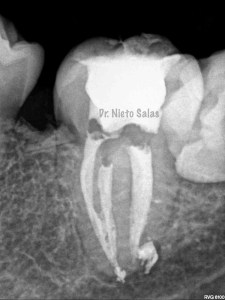

Así pues quedaría el sellado hermético y tridimensional:

La otra pieza, el 3.7, se instrumentó con sistema Protaper y obturación con Ola continua de Calor y un back-filling con la pistola Obtura II.